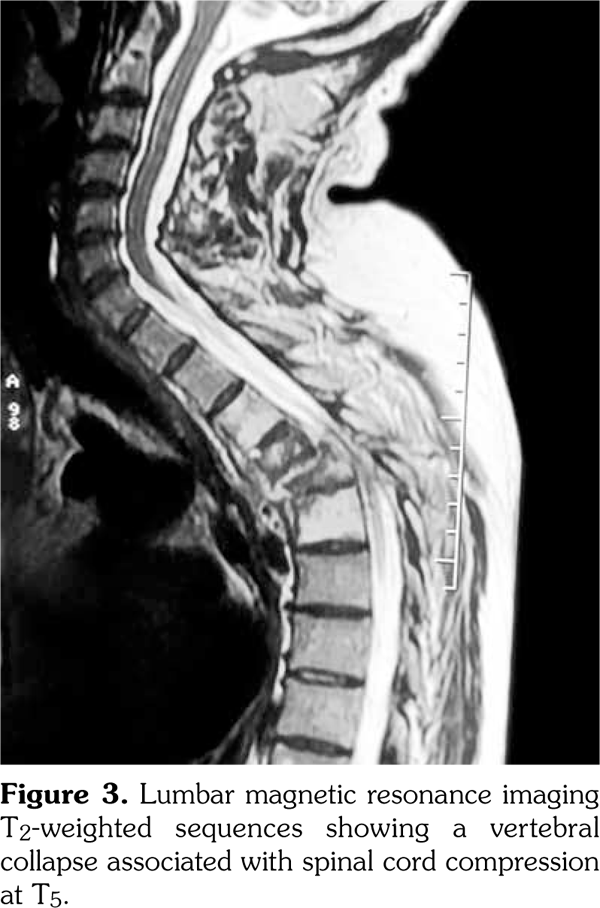

Laboratory examination revealed a slightly elevated C-reactive protein level (16 mg/L) and erythrocyte sedimentation rate (40 mm). Serum levels of calcium, albumin and phosphorus were within the normal range. Blood cell counts, liver tests, and renal function were unremarkable. Blood cultures, urinanalysis, tumor markers, and serodiagnosis for brucella were negative. Tuberculosis skin test was negative. Spine magnetic resonance imaging showed low T1, high T2 signal and contrast enhancement in the T4/T5 and L3 vertebral body and in the T4/T5 disk (Figure 1). Sacroiliac joints were normal. Computed tomography-guided biopsy of the T4/T5 disc demonstrated nonspecific inflammation and culture of this specimen was negative. Computed tomography scan of the sternoclavicular joints revealed hyperostosis and erosions involving the sternum as well as medial end of clavicle (Figure 2). Clavicular biopsy showed irregular sclerotic trabeculae. Human leukocyte antigen B27 typing was positive.